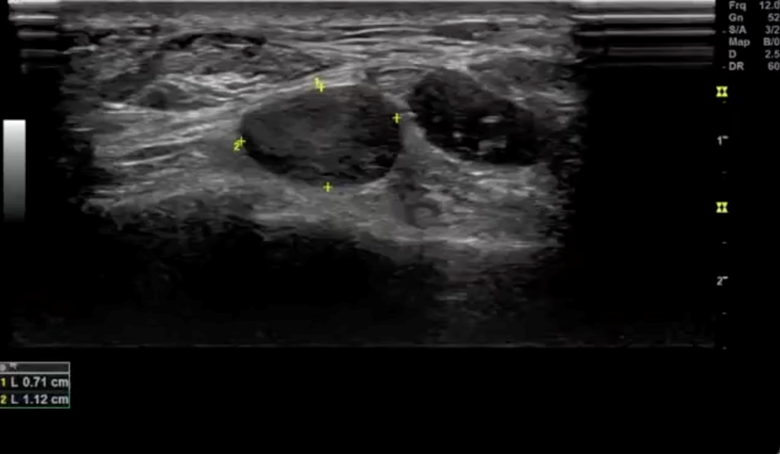

Image Interpretation: LAX view, ill-defined mass abutting the anterior tibial artery between the tibialis anterior and extensor hallucis longus tendons. 2.7 x 0.8 x 1.1 cm. Notable blood flow proximally and within mass observed with Doppler.

Teaching Pearl: Glomus tumors typically present in the upper extremities (particularly the hand/fingers) and as such can often be difficult to diagnose in other parts of the body. Patients with glomus tumors often have pinpoint tenderness, paroxysmal pain, and cold sensitivity. Clinical diagnosis can be tricky as those three characteristics are often isolated and less frequently occur together. US/MRI are the diagnostic imaging modalities of choice. US with doppler can be helpful in diagnosis as they can be mistaken for other benign masses and can help assist in the evaluation of an arterial supply feeding the tumor. A case series from the Hospital for Special Surgery (HSS) over the course of 18 years excised 11 glomus tumors from the foot, with the majority of them located in the distal hallux.1 The glomus tumor from this case matches descriptions of other extradigital glomus tumors, including a "vascular stack", however it is larger in size compared to the mean size (1 cm) from a study analyzing non-subungal glomus tumors.2 Typical glomus tumors are visualized as small, well-circumscribed, hypoechoic nodule with prominent arterial flow (vascular stalk).